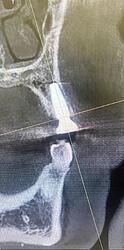

Placed #12 implant today . Looks like I placed the implant too buccally. Should I reposition ? Implant size is 4.3x13mm . Torque-40 ncm.

Definitely don’t remove/reposition and I would suggest stop evaluating placement via CBCT because doing so will almost always show lack of buccal bone. Years ago I heard Scott Ganz lecture about how CBCT “always” underestimates buccal bone… in other words there is “always” more buccal bone present than what appears on the image. As wonderful as advanced imaging is it will never replace direct visualization. Not sure if you placed this guided and flapless but I was taught and I still believe that a person should place a minimum of 100 fixtures conventionally before they resort to AI surgery. In this situation the quality/quantity of the overlying soft tissue is more important than the thickness of the buccal bone anyway. Nice work!!!

Implant was placed free hand after reflecting the flap. Also visually it looked like I had 1.5-2 mm bone . I will double check with perio probe when pt comes back

You did have 1.5-2mm of buccal bone then because you visualized it and no you should not add graft material. CBCT is worthless for evaluating the buccal plate around a fixture and direct visualization doesn’t lie… IMHO CBCT machines are so popular in dentistry because they always justify another procedure with another expense. If that fixture has good surrounding soft tissue then it will be fine even if the CBCT image is accurate which direct visualization has already proven that it is not accurate. At the end of the day soft tissue is far more important for long term success than some radiographic simulation of white stuff that we refer to as bone.